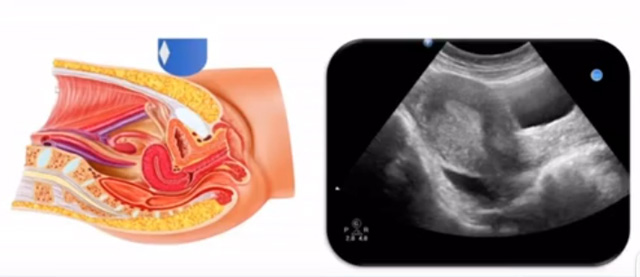

女性生殖系統(tǒng)包括內(nèi)、外生殖器官及其相關(guān)組織以及鄰近器官,其中內(nèi)生殖器是我們超聲檢查的主要對(duì)象。那么內(nèi)生殖器包括陰道、子宮還有輸卵管及卵巢。輸卵管及卵巢稱為子宮附件。子宮是倒置梨形,但是它是空腔厚壁肌性器官。它的正常值在育齡婦女。超聲探頭放在貼近腹壁盆腔上面位置,來(lái)看這個(gè)子宮在超聲上面的表現(xiàn)。從輪廓上來(lái)講,和示意圖是一樣的。這就是在超聲上面顯示的一個(gè)子宮的圖片。子宮在不同的時(shí)期與子宮頸的比例。成年婦女指的是育齡婦女為2:1子宮體是比較大的,嬰兒期為1:2說(shuō)明宮頸比較大,絕經(jīng)期1:1。所以我們?cè)诳吹阶訉m圖時(shí)候可以根據(jù)宮體宮頸比例大致可以推測(cè)屬于哪個(gè)時(shí)期的婦女。另外還可以根據(jù)比例大小來(lái)推斷是一個(gè)正常子宮還是異常子宮。

子宮從外到內(nèi),漿膜層、肌層、粘膜層。宮體部宮頸為梭形結(jié)構(gòu)。宮腔為上寬下窄的三角形,連接為峽部。子宮有什么功能呢?月經(jīng)血產(chǎn)生跟排出通道,精子運(yùn)行通道受精作用。囊胚著床及胎兒發(fā)育、生長(zhǎng)的場(chǎng)所。分娩時(shí)產(chǎn)生宮縮使胎兒、胎盤娩出。未孕的子宮是很小的,已孕子宮就非常大,平均胎兒都有6斤重。所以這個(gè)后壁就體現(xiàn)出來(lái)。輸卵管由子宮角部向外延伸,為一對(duì)細(xì)長(zhǎng)而彎曲的管道,呈管狀中空結(jié)構(gòu),大概長(zhǎng)度是8-14厘米,粗1-4毫米,它的下方為卵巢和闊韌帶。間質(zhì)部是厚一點(diǎn)的,峽部是比較窄的地方,壺腹部,漏斗部。正常情況下,輸卵管在普通超聲DR難以顯示。